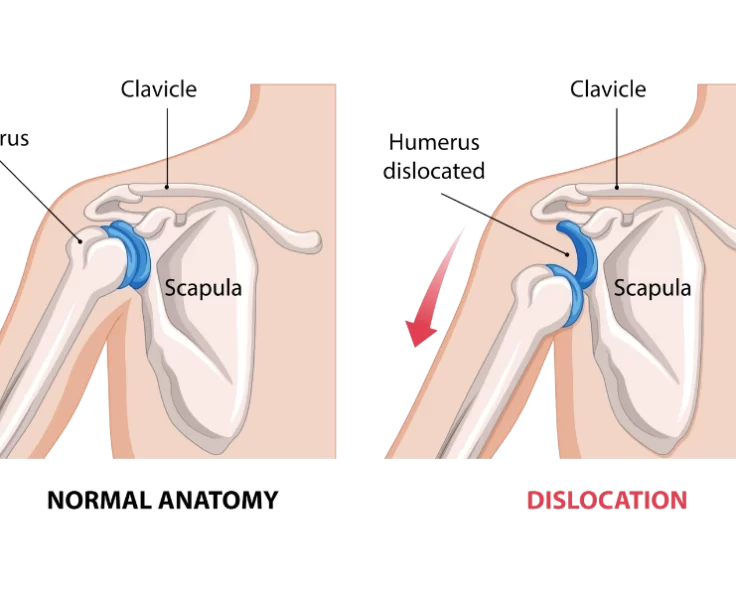

Bankart Repair

A Bankart Repair is a treatment that is used to avoid recurrent anterior shoulder dislocations caused by instability in the shoulder's rear.

AC Joint Dislocation

The shoulder is the most mobile joint in the body, it requires a complex system of structures to keep it stable during movement.

Shoulder Fracture Dislocation

Grade III dislocations can be treated conservatively, but surgery may be required in some cases. In a Grade III dislocation, the need for stabilisation surgery…